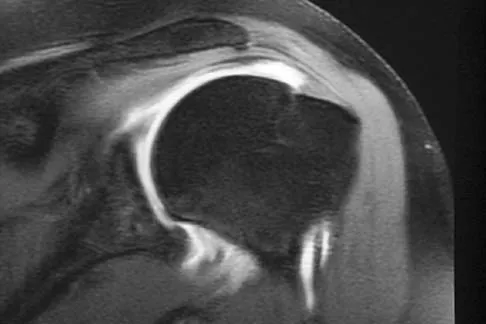

A 47-year-old male tennis player has pain in his nondominant shoulder that has failed to respond to 4 months of nonsurgical management. Examination reveals acromial tenderness and pain at the supraspinatus tendon insertion. He has a positive impingement sign, pain on forward elevation, and minimal cuff weakness. The MRI scans are shown in Figures 30a and 30b. To completely resolve his symptoms, treatment should consist of

Explanation